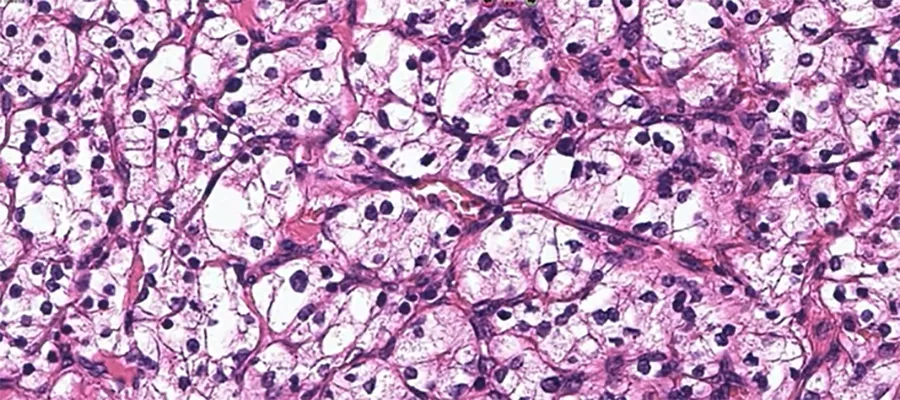

Histology section of ccRCC. Clear cell renal cell carcinoma is named after how the tumour looks under the microscope - the cells in the tumour look clear, like bubbles.

Kidney cancer (renal cell carcinoma or RCC) is the 7th most common type of cancer in the UK, accounting for 4% of new diagnoses. It is common in both man and women, and its incidence more than doubled in the developed world over the past half-century. Clear cell renal cell carcinoma (ccRCC), is the most frequent type of kidney cancer, accounting for about 80% of all RCC cases.